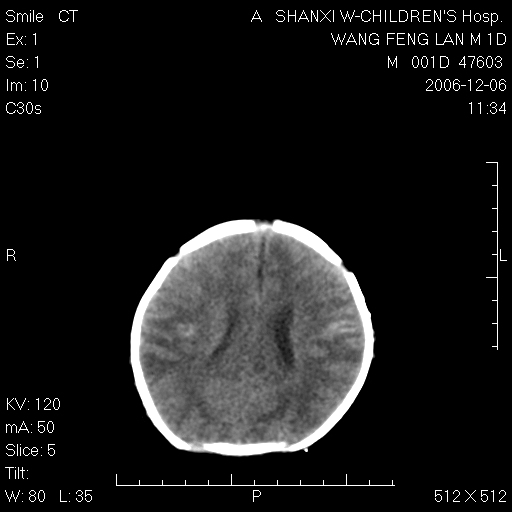

以下是引用zjzjr在2006-12-6 19:29:00的发言:[br]支持新生儿缺血缺氧性脑病伴少量蛛网膜下腔出血.

以下是引用卜一在2006-12-6 21:38:00的发言:[br][br] 支持:新生儿缺血缺氧性脑病伴少量蛛网膜下腔出血 [br]